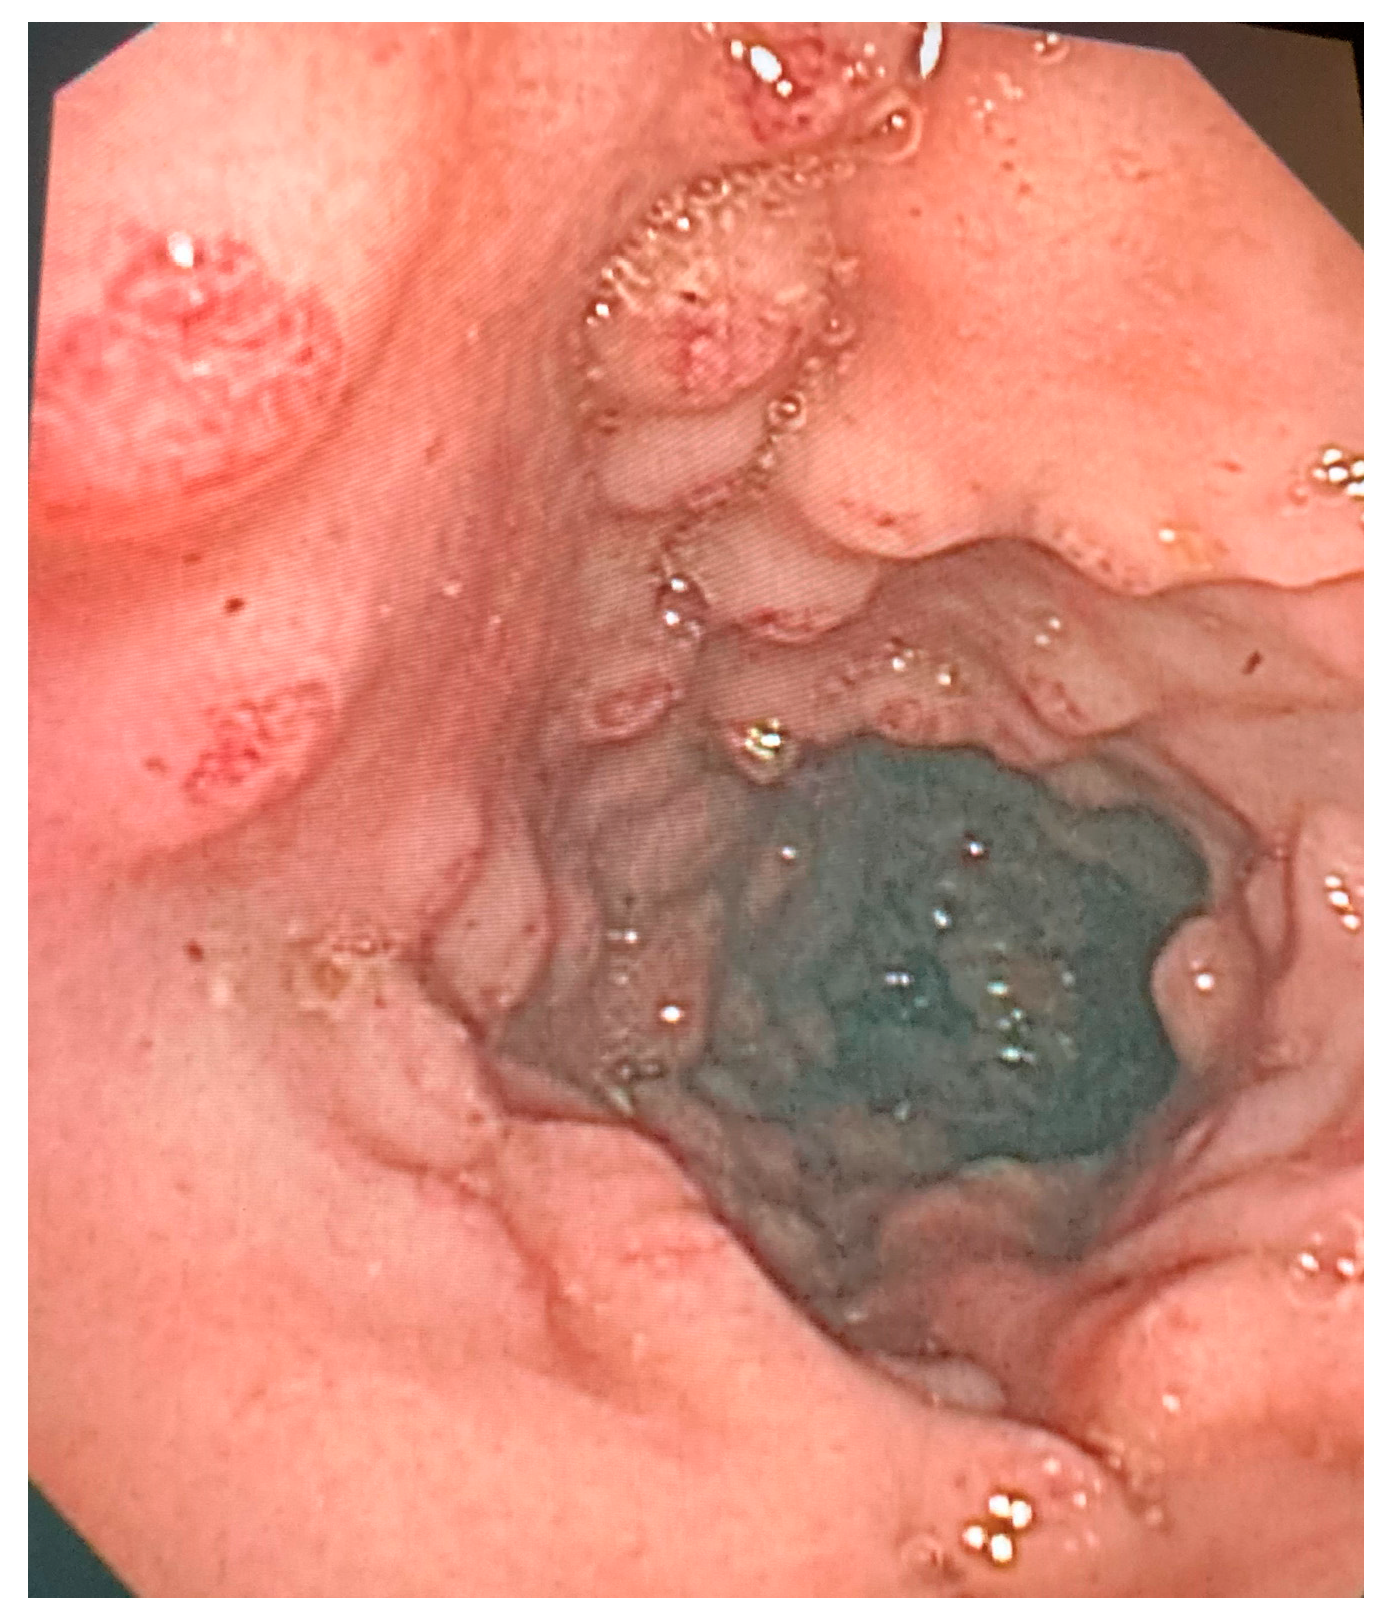

3. Results